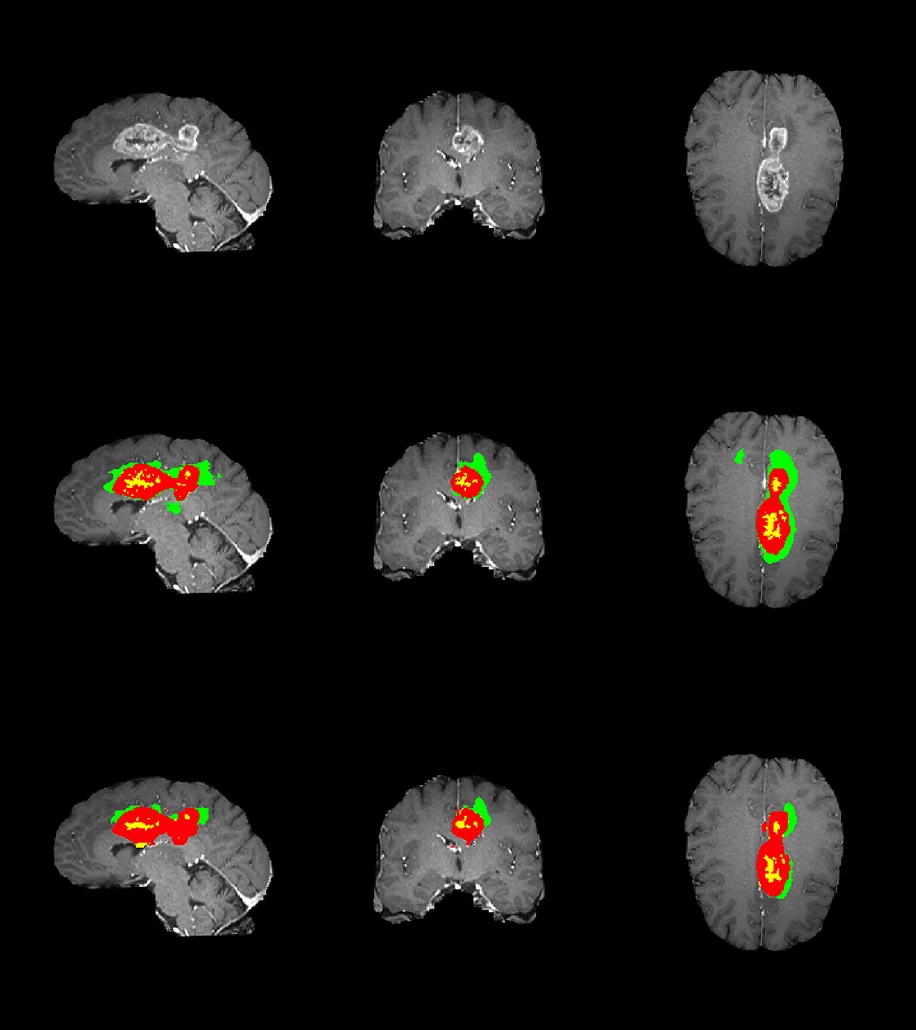

Medical image segmentation, on the other hand, goes a step further. Instead of simply identifying what exists, segmentation defines exactly where it exists—often down to individual pixels in 2D images or voxels in 3D scans like CT and MRI. This level of precision is critical for clinical applications where boundary accuracy directly affects model outcomes.

- Semantic segmentation: Classifies every pixel into a predefined category, useful for identifying broader anatomical regions.

- Instance segmentation: Differentiates between multiple instances of the same structure (e.g., multiple lesions).

- Pixel-level / Voxel-level segmentation: Provides high-precision boundaries essential for detecting subtle abnormalities and measuring progression.

- 3D volumetric segmentation: Applied to CT and MRI data, enabling spatial understanding across slices rather than isolated images.

In medical AI, annotation errors rarely stay local. Small boundary inconsistencies propagate through training and validation. (2)

The problem is not scale itself—it is scaling without the right expertise, processes, and flexibility. In medical AI, annotation errors do not stay isolated; they propagate through training, validation, and deployment, directly affecting model reliability and clinical confidence.